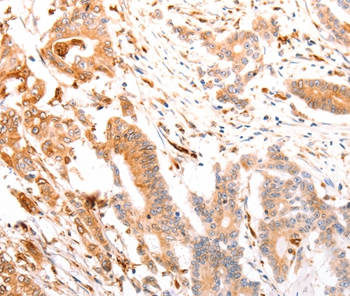

Immunohistochemical analysis of paraffin-embedded Human colon cancer tissue using #37305 at dilution 1/25.

Immunohistochemical analysis of paraffin-embedded Human thyroid cancer tissue using #37305 at dilution 1/25.